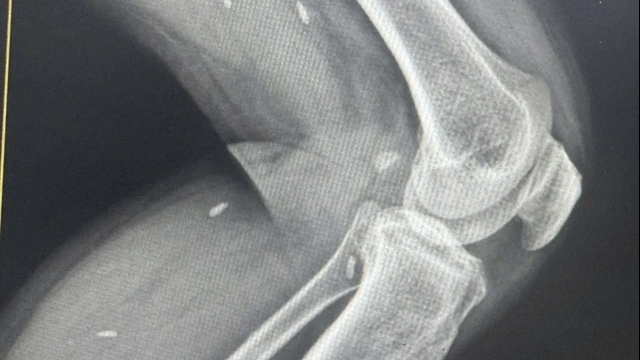

| Phim chụp thanh sắt xuyên thấu từ vùng cổ sau, xuyên qua xương sọ vùng chẩm, xuyên vào tiểu não và đi ra ngoài phía xương sọ. Ảnh: BVCC |

Bệnh nhân được đưa đến viện trong tình trạng lơ mơ, hoảng loạn. Các bác sĩ tua trực của Bệnh viện Hữu nghị Việt Đức đã cấp cứu khẩn trương, đánh giá phối hợp đa chuyên khoa: bác sĩ phẫu thuật thần kinh, phẫu thuật cột sống, phẫu thuật tim mạch, bác sĩ gây mê hồi sức. Do bệnh nhân đến cùng dị vật dài 1m cắm vào vùng cổ nên không thể thực hiện chụp cắt lớp vi tính, đội ngũ bác sĩ hoàn toàn dựa vào khám lâm sàng và chụp X-quang, những phương pháp chẩn đoán cơ bản nhất để đánh giá kỹ lưỡng và đưa ra quyết định quan trọng cho bệnh nhân.